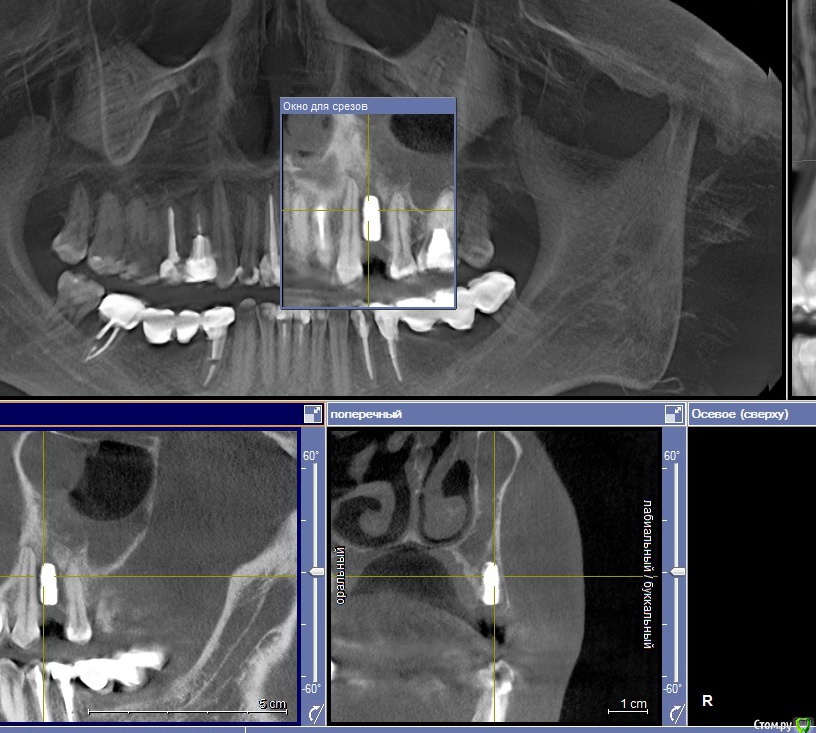

krokomot Опубликовано 5 апреля, 2016 Поделиться Опубликовано 5 апреля, 2016 а со снимком что? 1 Ссылка на комментарий

Военный Врач Опубликовано 6 апреля, 2016 Автор Поделиться Опубликовано 6 апреля, 2016 а со снимком что? Ссылка на комментарий